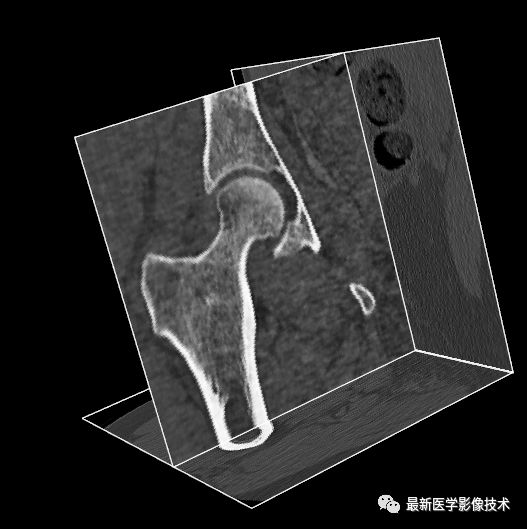

首先,我们输入原始MR图像。